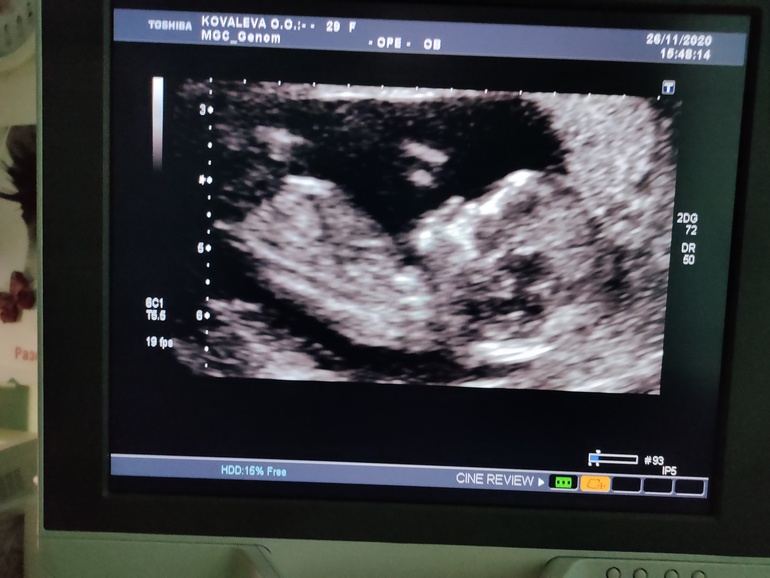

Наше первое фото (1 скрининг)

Смеялась, когда увидела как он дёргается, плавает и вообще не ожидала увидеть очертания уже вполне себе человека. Нам 12 недель,

Рост 4 см и у нас есть нос и ушки🤗🤗🤗😄😄